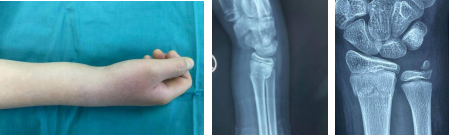

当天,betway在线登陆二病区齐伟亚主任手术团队刘桂谦医师在值班,刘桂谦医生接诊患儿后,经查体、x线示右桡骨远端骨折,右尺骨茎突骨折,断端错位。父母十分担心孩子以后的身体发育及右腕活动。

术前

齐伟亚主任手术团队结合政政的病情、骨折部位及年龄情况,决定为其使用闭合复位微创Ilizarov技术迷你外架,这样考虑的原因是微创、固定牢靠、不跨关节、不破坏骨骺、抗旋转、可加压、弹性固定,无需二次手术取出内固定;尤其适用于急性损伤或者手法复位后骨折端再次移位的患者,以及多次手法复位不能成功的患儿。

术后即刻

术中一切顺利,闭合复位后,微创Ilizarov技术迷你外架固定,术后X线显示骨折端对位对线好,术后无需石膏外固定,早期进行康复功能锻炼。